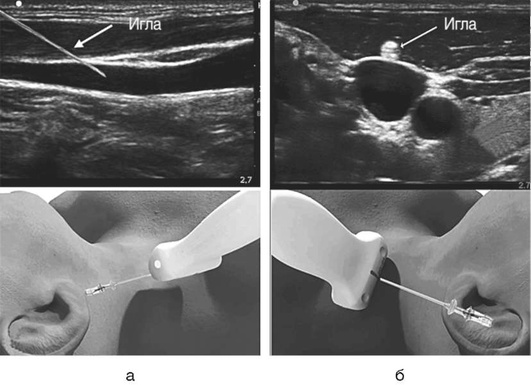

Катетеризация центральных вен

Показания к установке центрального венозного катетера (ЦВК).

ОСНОВНЫЕ ПОЛОЖЕНИЯ Выбор доступа